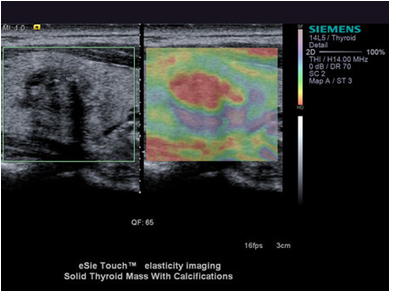

В основу волновой эластографии заложена возможность исследования эластичности мягких тканей. В отличие от доброкачественных опухолей, злокачественные — плотные, не эластичные и с трудом поддаются компрессии. На мониторе аппарата УЗИ более плотные ткани окрашены в голубой и синий цвета, жировая ткань приобретает желто-красный оттенок, а соединительная ткань — зеленый. Высокая специфичность метода позволяет избежать необоснованных биопсий. После прохождения УЗИ с эластографией пациент получает на руки развернутое заключение, в котором врач описывает: размер и положение исследуемого органа, наличие, размер и плотность новообразований, наличие и стадию фиброзных изменений, рекомендации по дальнейшему наблюдению у нужного специалиста.